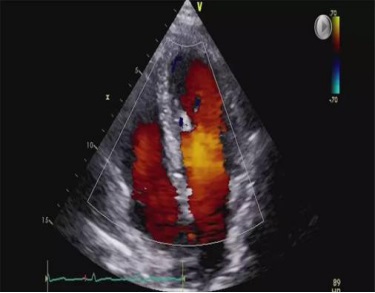

“医生,仪器屏幕上咋个没得彩色图像喃?你们这个是不是彩超哦?”相信每个患者都思考过类似提问。随着医疗条件的不断发展,现大多运用彩色超声仪为病人检查。但是,为什么医生看着的屏幕和家里的彩色电视机差别很大呢?彩超中“彩色”两字的含义通俗地说其实是为了提示血管的血流方向,一般有红色和蓝色两种。

医生通过血流方向判断目标脏器是否有血供以及血流方向以协助诊断疾病。所以说,彩超是彩色的,但是不等同于您家里的彩色电视机。